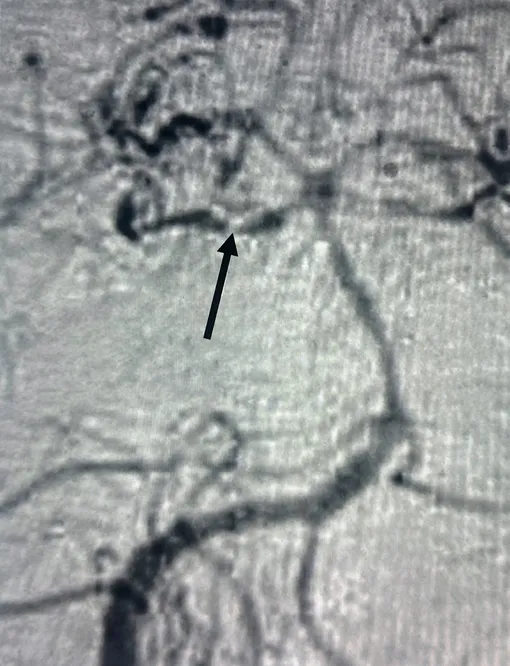

Обследование показало ишемический инсульт: кровоснабжение было нарушено в зоне мозга, отвечающей за движение и чувствительность.